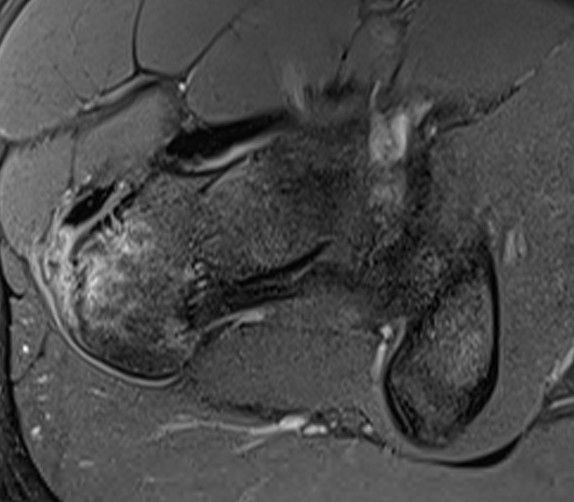

Intact gluteus medius insertion

Torn gluteus medius and minimus

Acute tear gluteus medius